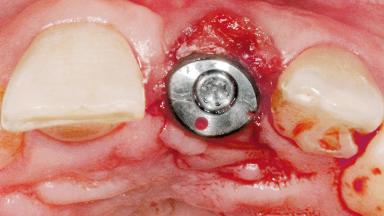

Late Flapless Placement of an Implant in a Maxillary Left Central Incisor Site

A 39-year-old male patient presented with a chief complaint of discomfort and gingival discoloration around his maxillary left central incisor. He was in good general health and was a non-smoker. His past dental history was significant because of the traumatic fracture of tooth 21 in a sporting accident at age 13. Initial dental treatment included endodontic therapy and a full-coverage restoration. The patient became symptomatic 5 years later, when structural failure of the tooth resulted in the dislodgment of the crown. Endodontic retreatment, apical surgery, and post-and-core restoration were performed.

| Bone Volume | Deficient horizontally, requiring prior grafting |